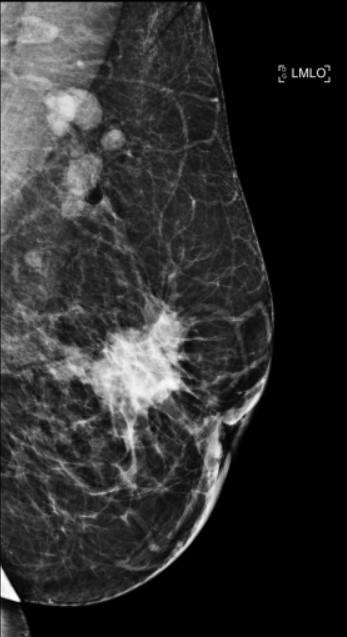

An Opportunistic screening mammography dataset from a screening-naive population

2024-09-10

63GB

MAMOS_1000000004

3577

252

237

Quick View

Data

PGIMER-IITKGP mammogram database images for microcalcification

2026-04-16

535MB

MAMOS_1000000030

110

16

4